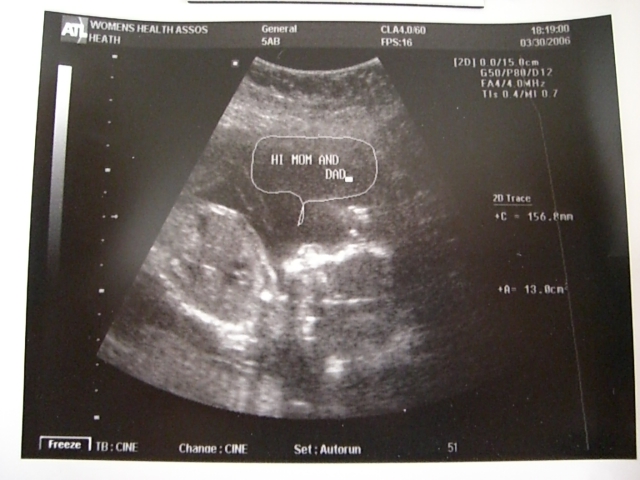

Spike at 19 weeks